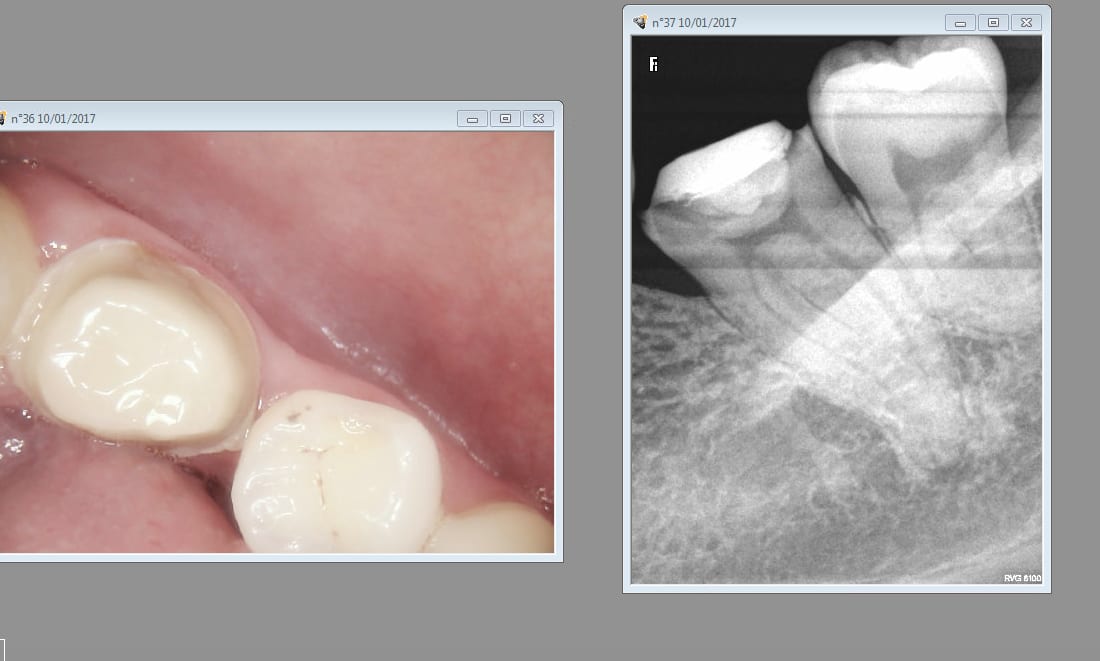

La patiente ( nouvelle patiente) a trainé s'est décidée à reprendre RDV. En effet sa dent ( jadis vivante) commence à la titiller. On se demande pourquoi. -)

Tu vois casa cette patiente ( nouvelle patiente) qui a consulté pour une 45 fracturée ( d'ailleurs on ne se demande pas pourquoi elle s'est fracturée lol !) ne s'est pas plainte du fait que j'ai commencé par soigner 16 et 17 au premier RDV. -)

Par contre contrairement au cas précédent, un devis a été établi au premier RDV.

Mais bien sur il ne sert à rien de regarder ailleurs et de faire un bilan complet ! je viens pour une dent cassée et vous me soignez 2 autres qui ne me font pas mal !? C'est quoi ce travail docteur ?